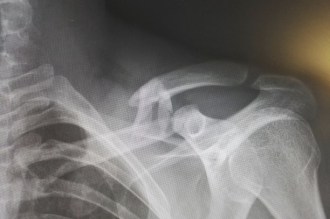

Si tienes alguno de estos síntomas, debes acudir a los servicios médicos de urgencias. Para realizar el diagnóstico y prescribir el tratamiento oportuno, deberán hacer una radiografía en la que identifiquen el tipo de lesión y su localización. Las fracturas de clavícula se clasifican de manera diferente según el lugar exacto en el que se haya dado, el desplazamiento o la presencia o ausencia de fragmentos.

Se prescribirá un tratamiento acorde al tipo de fractura que se haya producido: de tercio medio, de tercio proximal o de tercio distal. Esta última, por ejemplo, lleva asociada una rotura de los ligamentos que motiva que la clavícula se desplace hacia arriba, por lo que se suele requerir tratamiento quirúrgico.